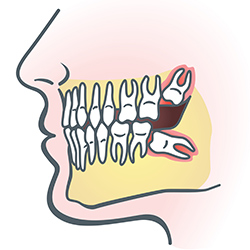

Wisdom teeth are types of

molars found in the very back of your mouth. These teeth usually appear in late

teens or early twenties but may become impacted (fail to erupt) due to lack of

room in the jaw or angle of entry. When a wisdom tooth is impacted, it may need

to be removed. If it is not removed, you may develop gum tenderness, swelling,

or even severe pain. Impacted wisdom teeth that are partially or fully erupted

tend to be quite difficult to clean and are susceptible to tooth decay,

recurring infections, and even gum disease.

Wisdom teeth are typically removed in the late teens or early twenties because there is a greater chance that the teeth's roots have not fully formed and the bone surrounding the teeth is less dense. These two factors can make extraction easier, as well as making the recovery time much shorter.

In order to remove a wisdom tooth, your dentist first needs to numb the area around the tooth with a local anesthetic. Since the impacted tooth may still be under the gums and imbedded in your jaw bone, your dentist will need to remove a portion of the covering bone to extract the tooth. In order to minimize the amount of bone that is removed with the tooth, your dentist will often "section" your wisdom tooth so that each piece can be removed through a small opening in the bone. Once your wisdom teeth have been extracted, the healing process begins. Healing time varies depending on the degree of difficulty related to the extraction. Your dentist will share with you what to expect and provide instructions for a comfortable, efficient healing process.